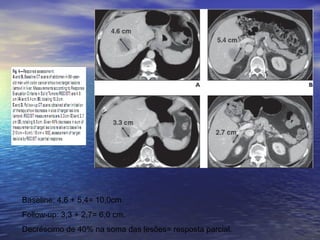

Baseline: 4,6 + 5,4= 10,0cm.

Follow-up: 3,3 + 2,7= 6,0 cm.

Decréscimo de 40% na soma das lesões= resposta parcial.